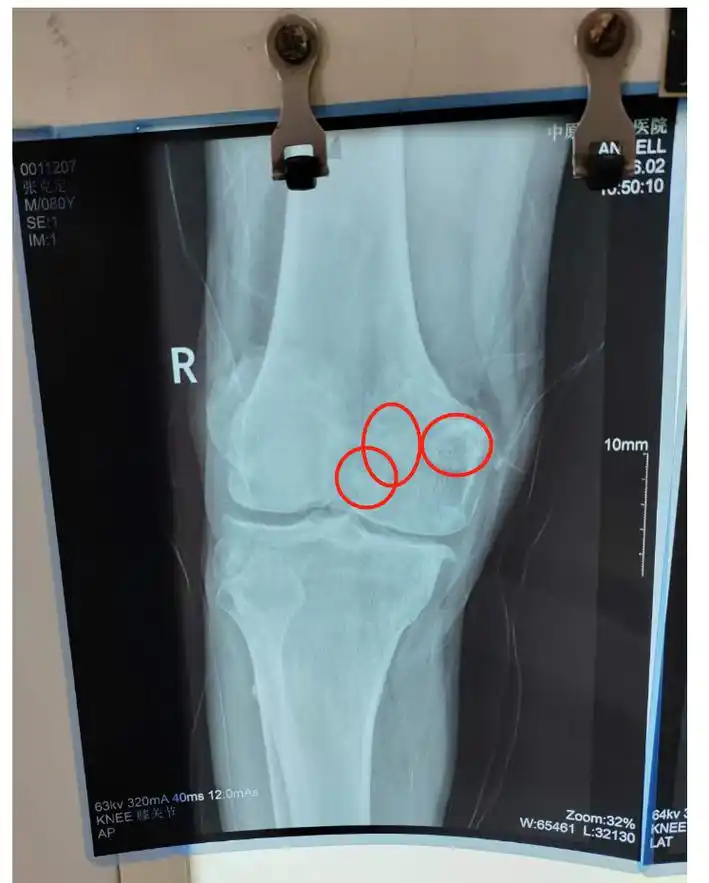

小心出现这些症状可能是关节鼠在作怪

7只关节鼠折磨他5年膝盖经常咔咔响小心关节鼠正流窜

罕见!小小膝盖竟长了近30颗"关节鼠"

原创鼠年谈鼠骨哥崔大夫膝关节系列第二回关节鼠